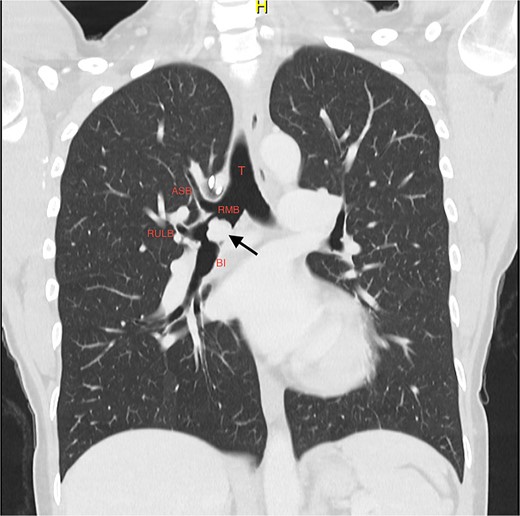

A 37-year-old woman presented with progressive wheeze and shortness of breath. She had been given multiple courses of antibiotics and steroids with only temporary relief. She had been a recent ex-smoker and had no prior medical history. There were no symptoms of carcinoid syndrome. Computed tomography (CT) and positron emission tomography (PET) imaging demonstrated a polypoid mass in the bronchus intermedius, suspicious for a carcinoid tumour (Fig. 1).

Coronal slice of CT thorax pre-bronchoscopy, showing polypoid tumour arising from the bronchus intermedius and the right upper lobe apical segmental bronchus arising from the RMB at the level of the carina; the arrow is pointing to the tumour; T, trachea; RMB, right main bronchus; ASB, apical segmental bronchus; RULB, right upper lobe bronchus; BI, bronchus intermedius.